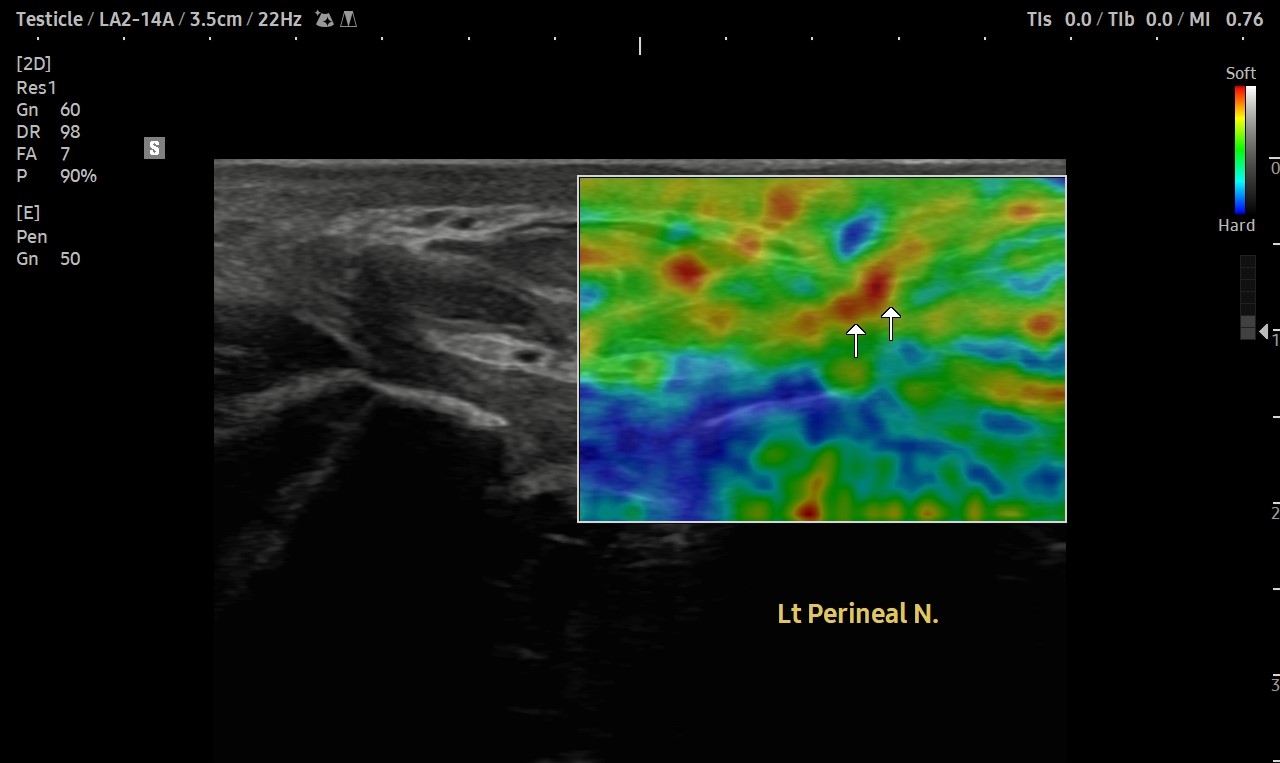

[치료 전]

[치료 후]

- 치료횟수 : 30 회